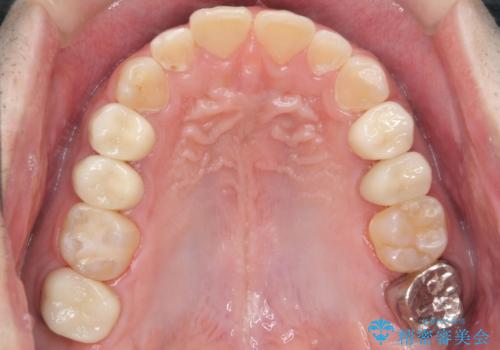

総合歯科治療 → 歯周病治療&インプラント治療

歯がボロボロで咬合崩壊 矯正・インプラント・セラミックで実現する、酸蝕症の総合治療